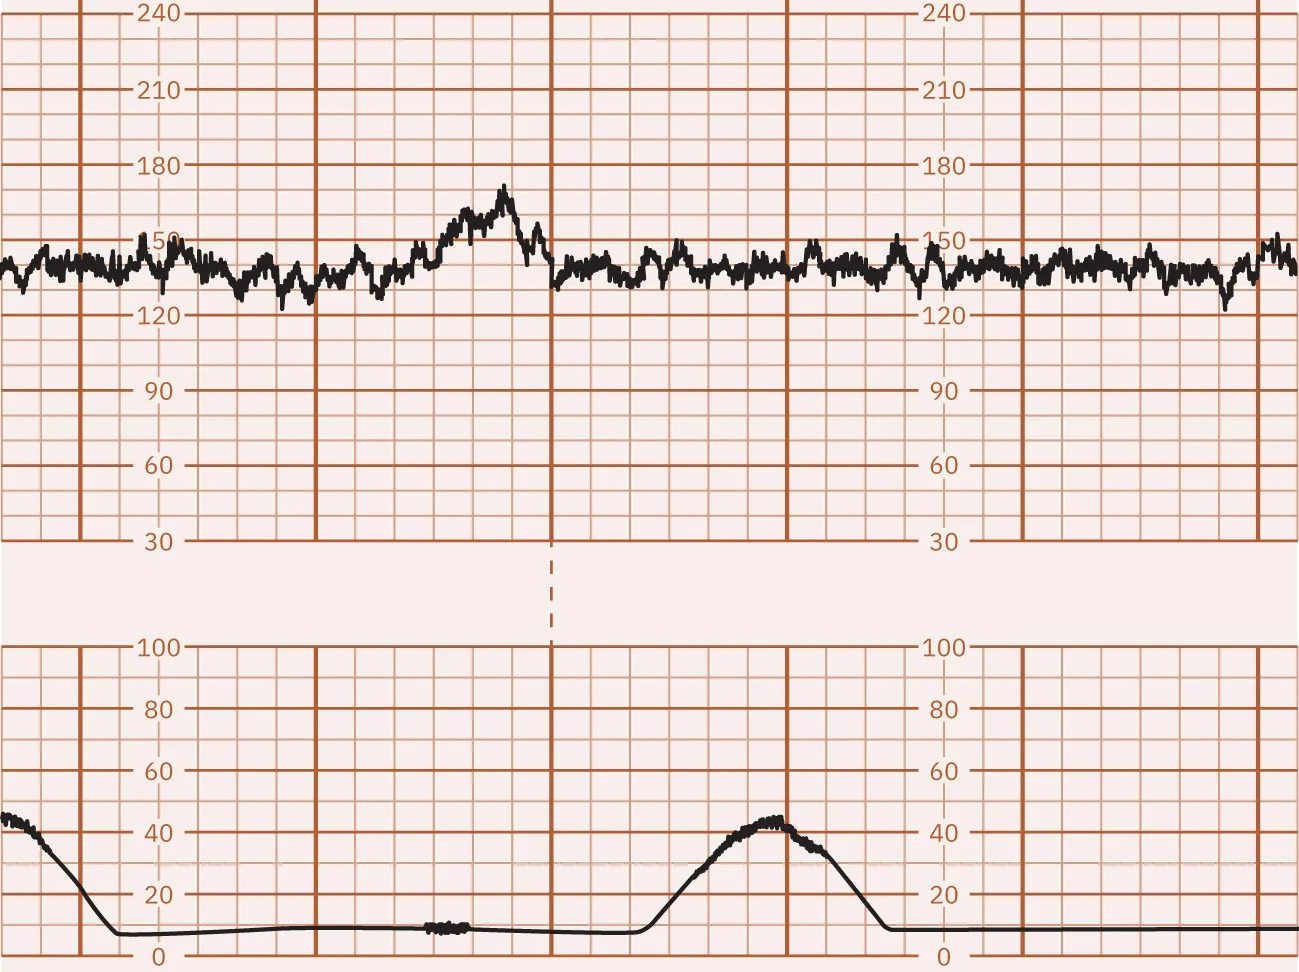

Variable Decelerations

Abrupt decelerations of the FHR of at least 15 bpm below the baseline that last at least 15 to 30 seconds are called variable decelerations. They do not typically appear in a pattern and vary in onset, depth, and duration. Variable decelerations are caused by compression of the umbilical cord. Cord compression can be caused by a fetal body part squeezing the cord against the wall of the uterus during a uterine contraction or movement related to the pregnant person or fetus. Because of this, the nurse will notice that variable decelerations may or may not occur in conjunction with uterine contractions. Variable decelerations may lead to fetal hypoxia, especially when they are repetitive for a prolonged period. Figure 16.13 shows a monitor tracing with an example of variable decelerations.

Fetal heart rate reading indicating variable decelerations.

Figure 16.13 Variable FHR Decelerations Variable decelerations appear with the contractions making a โ€œVโ€ or โ€œWโ€ shape. (attribution: Copyright Rice University, OpenStax, under CC BY 4.0 license)